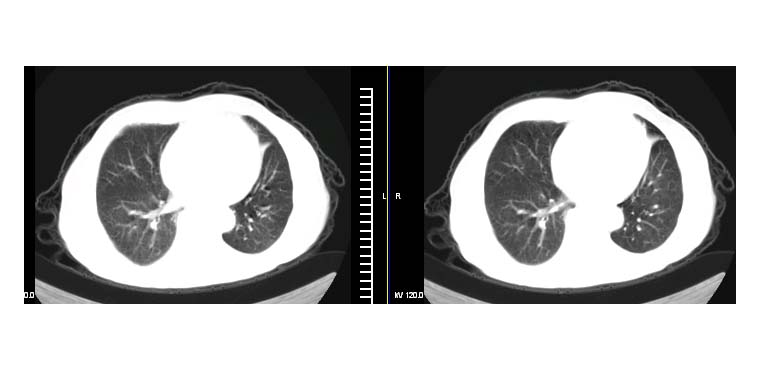

标题: CT11087:男性,82.咳嗽一周.抗炎治疗4-5天效果不明 [打印本页]

标题: CT11087:男性,82.咳嗽一周.抗炎治疗4-5天效果不明

病人年龄偏大,不除外为恶性病变。

考虑左上肺癌(病灶有分叶,毛刺)可能性大.

考虑左上肺周围性肺癌(实性病灶有分叶,毛刺)可能性大。